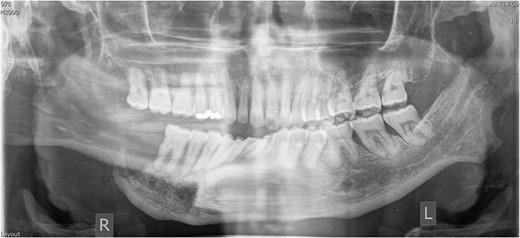

On radiographic examination, there was complete bone loss of the right mandible up to the lower right first molar and also bone loss affecting the left coronoid and ramus (Fig. 1). Previous radiographic reports from 2013 had shown only bone loss of the right ramus. The patient was subsequently referred for a CT scan of his facial bones, which he failed to attend. As was the case with the previous department, he failed to attend appointments with the metabolic bone disease unit for further investigation of other bones. He was also prescribed alendronic acid, a bisphosphonate, in 2014 but did not fill the prescription.

Dental panoramic tomograph from 2016 showing extensive bone loss of the right mandible, left coronoid process and ramus.